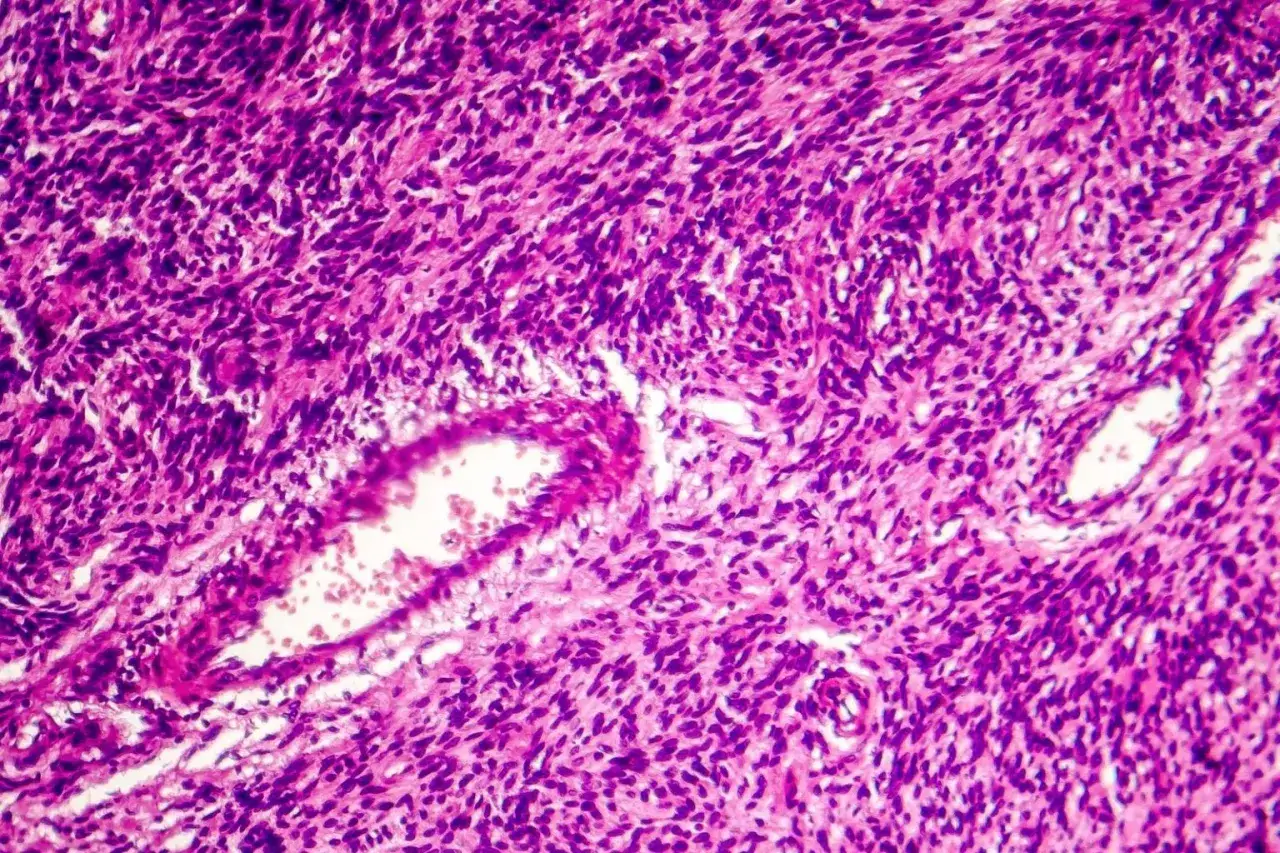

Sam wygląd guzka nie wystarcza. W przypadku zmian wrzecionowatokomórkowych wynik badania cytologicznego bywa mało jednoznaczny, dlatego zwykle potrzebna jest biopsja z oceną histopatologiczną. To właśnie mikroskopowe badanie tkanki pozwala odróżnić nowotwór od stanu zapalnego, blizny czy innego rodzaju zmiany.